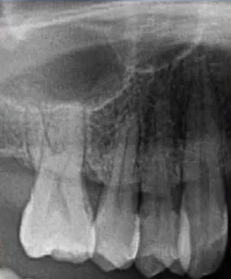

32岁,男性,因咬物不适来院就诊。

查:14残根,牙龈红肿;35叩诊(+),45叩诊(+),牙颌面见畸形中央尖。

35叩诊(+)

二次拍根尖片确认可看到根尖低密度炎症,临床检查与影像学检查相符,是根尖周炎。

曲面断层片怎么看口腔精读 | 一次性教你看懂曲面断层片!_https://www.jmylbn.com_新闻资讯_第21张

临床检查时发现14残根,牙龈红肿。曲面断层片上由于前磨牙转角问题,看不到残根,无法明确到底有没有残根,无法通过曲面断层片进行确诊或评估。

这时需要加拍根尖片,很明显能看到残根。这就说明,有曲面断层片也不能排除情况。

临床检查45叩诊(+),牙颌面见畸形中央尖。加拍根尖片可看到,右下5根方有低密度影,并且右下5的牙根较短小,和曲面断层片上显示的大小不同,所以右下5是舌向倾斜的牙齿。